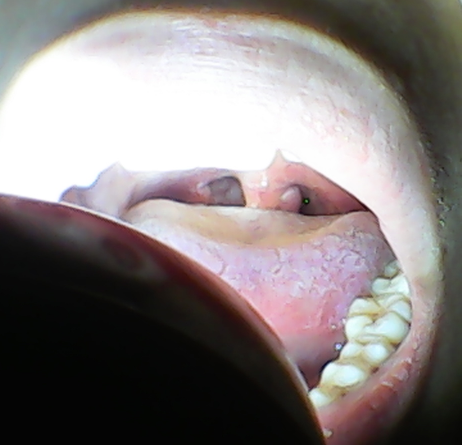

喉咙小舌头有一个球 不疼不痒不影响吃东西 只是咽东西的时候感觉不

好像是悬雍垂旁边又多了一个小疙瘩,而且平时小疙瘩旁边还有